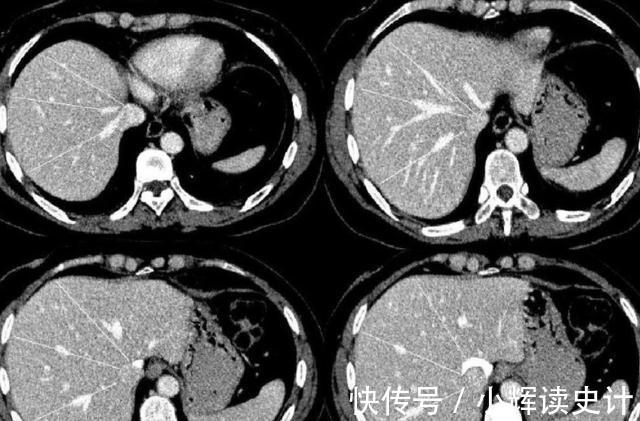

影像学检查正常

影像检查也是癌症患者经常需要做的一项检查,项目影像检查包括胸片,ctpet-CT骨扫描等多种检查项目,通过影像学检查可以更加清楚的看到患者的病灶情况,并且能够看到患者病灶是否出现转移的可能性,通过影像学检查可以更加了解病灶位置的康复情况,能够判断患者身体当中癌症是否出现转移或复发的可能性。